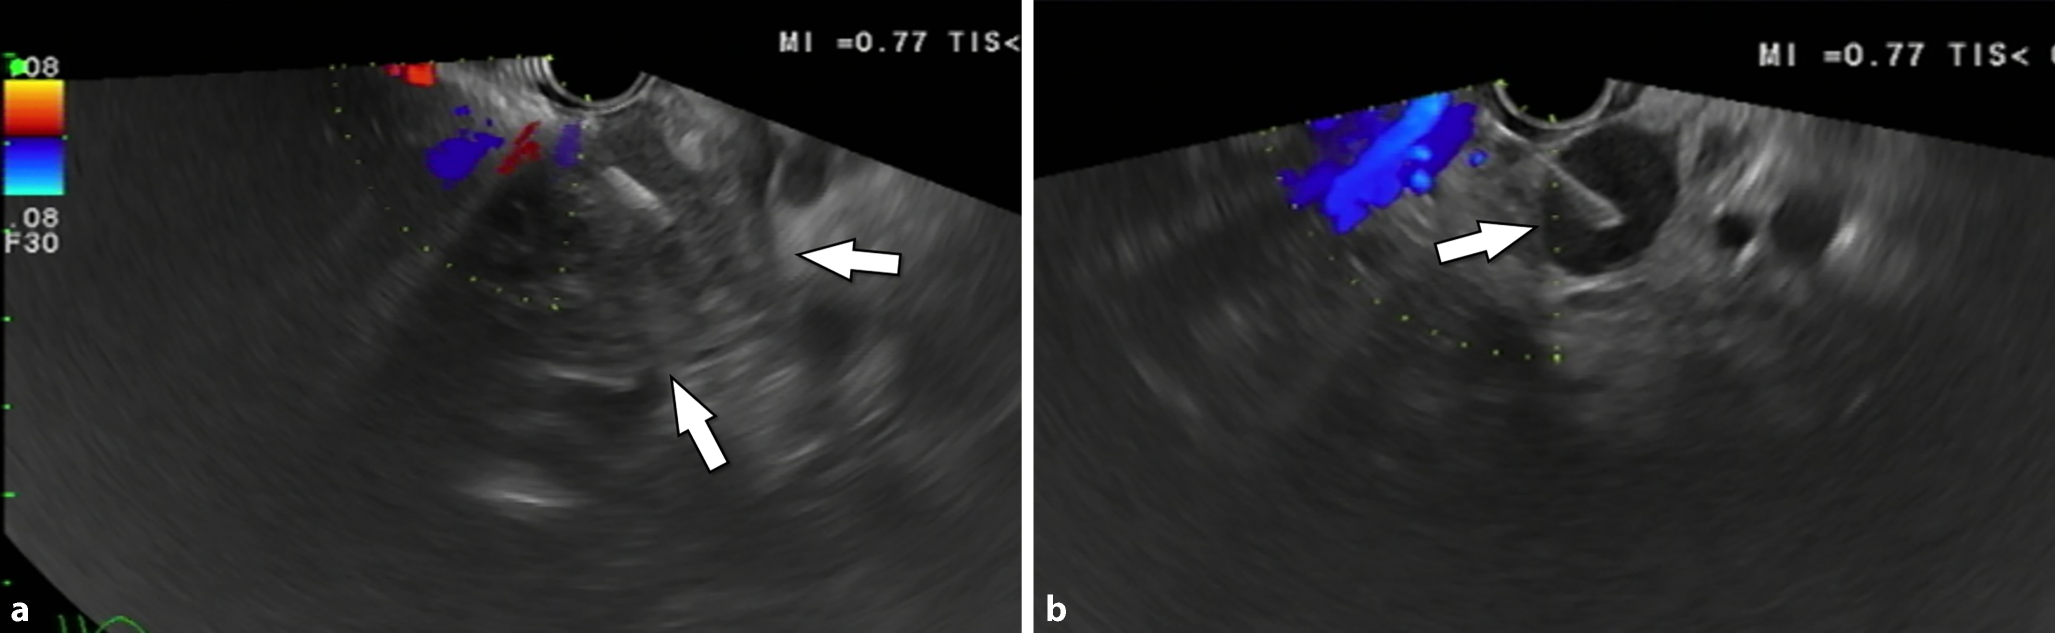

Abb. 2

a In der Endosonographie ist der Tumor schlecht abgrenzbar, überschreitet aber auf jeden Fall die Ösophaguswand (Pfeile). b Endosonographisch gezielte Biopsie eines 1,5 cm großen, suspekten lokoregionären Lymphknotens (Pfeil)